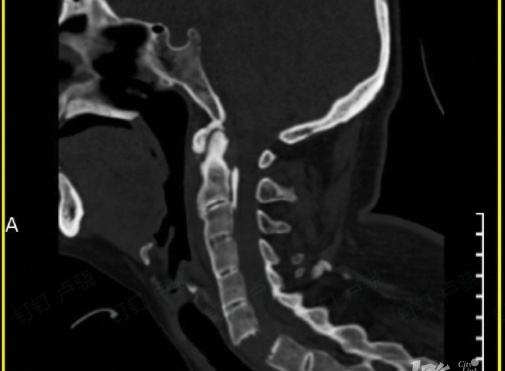

通过影像检查发现

刘女士颈椎6-7节完全断离

颈椎骨折造成脊髓损伤

导致全身瘫痪

(刘女士检查影像图)